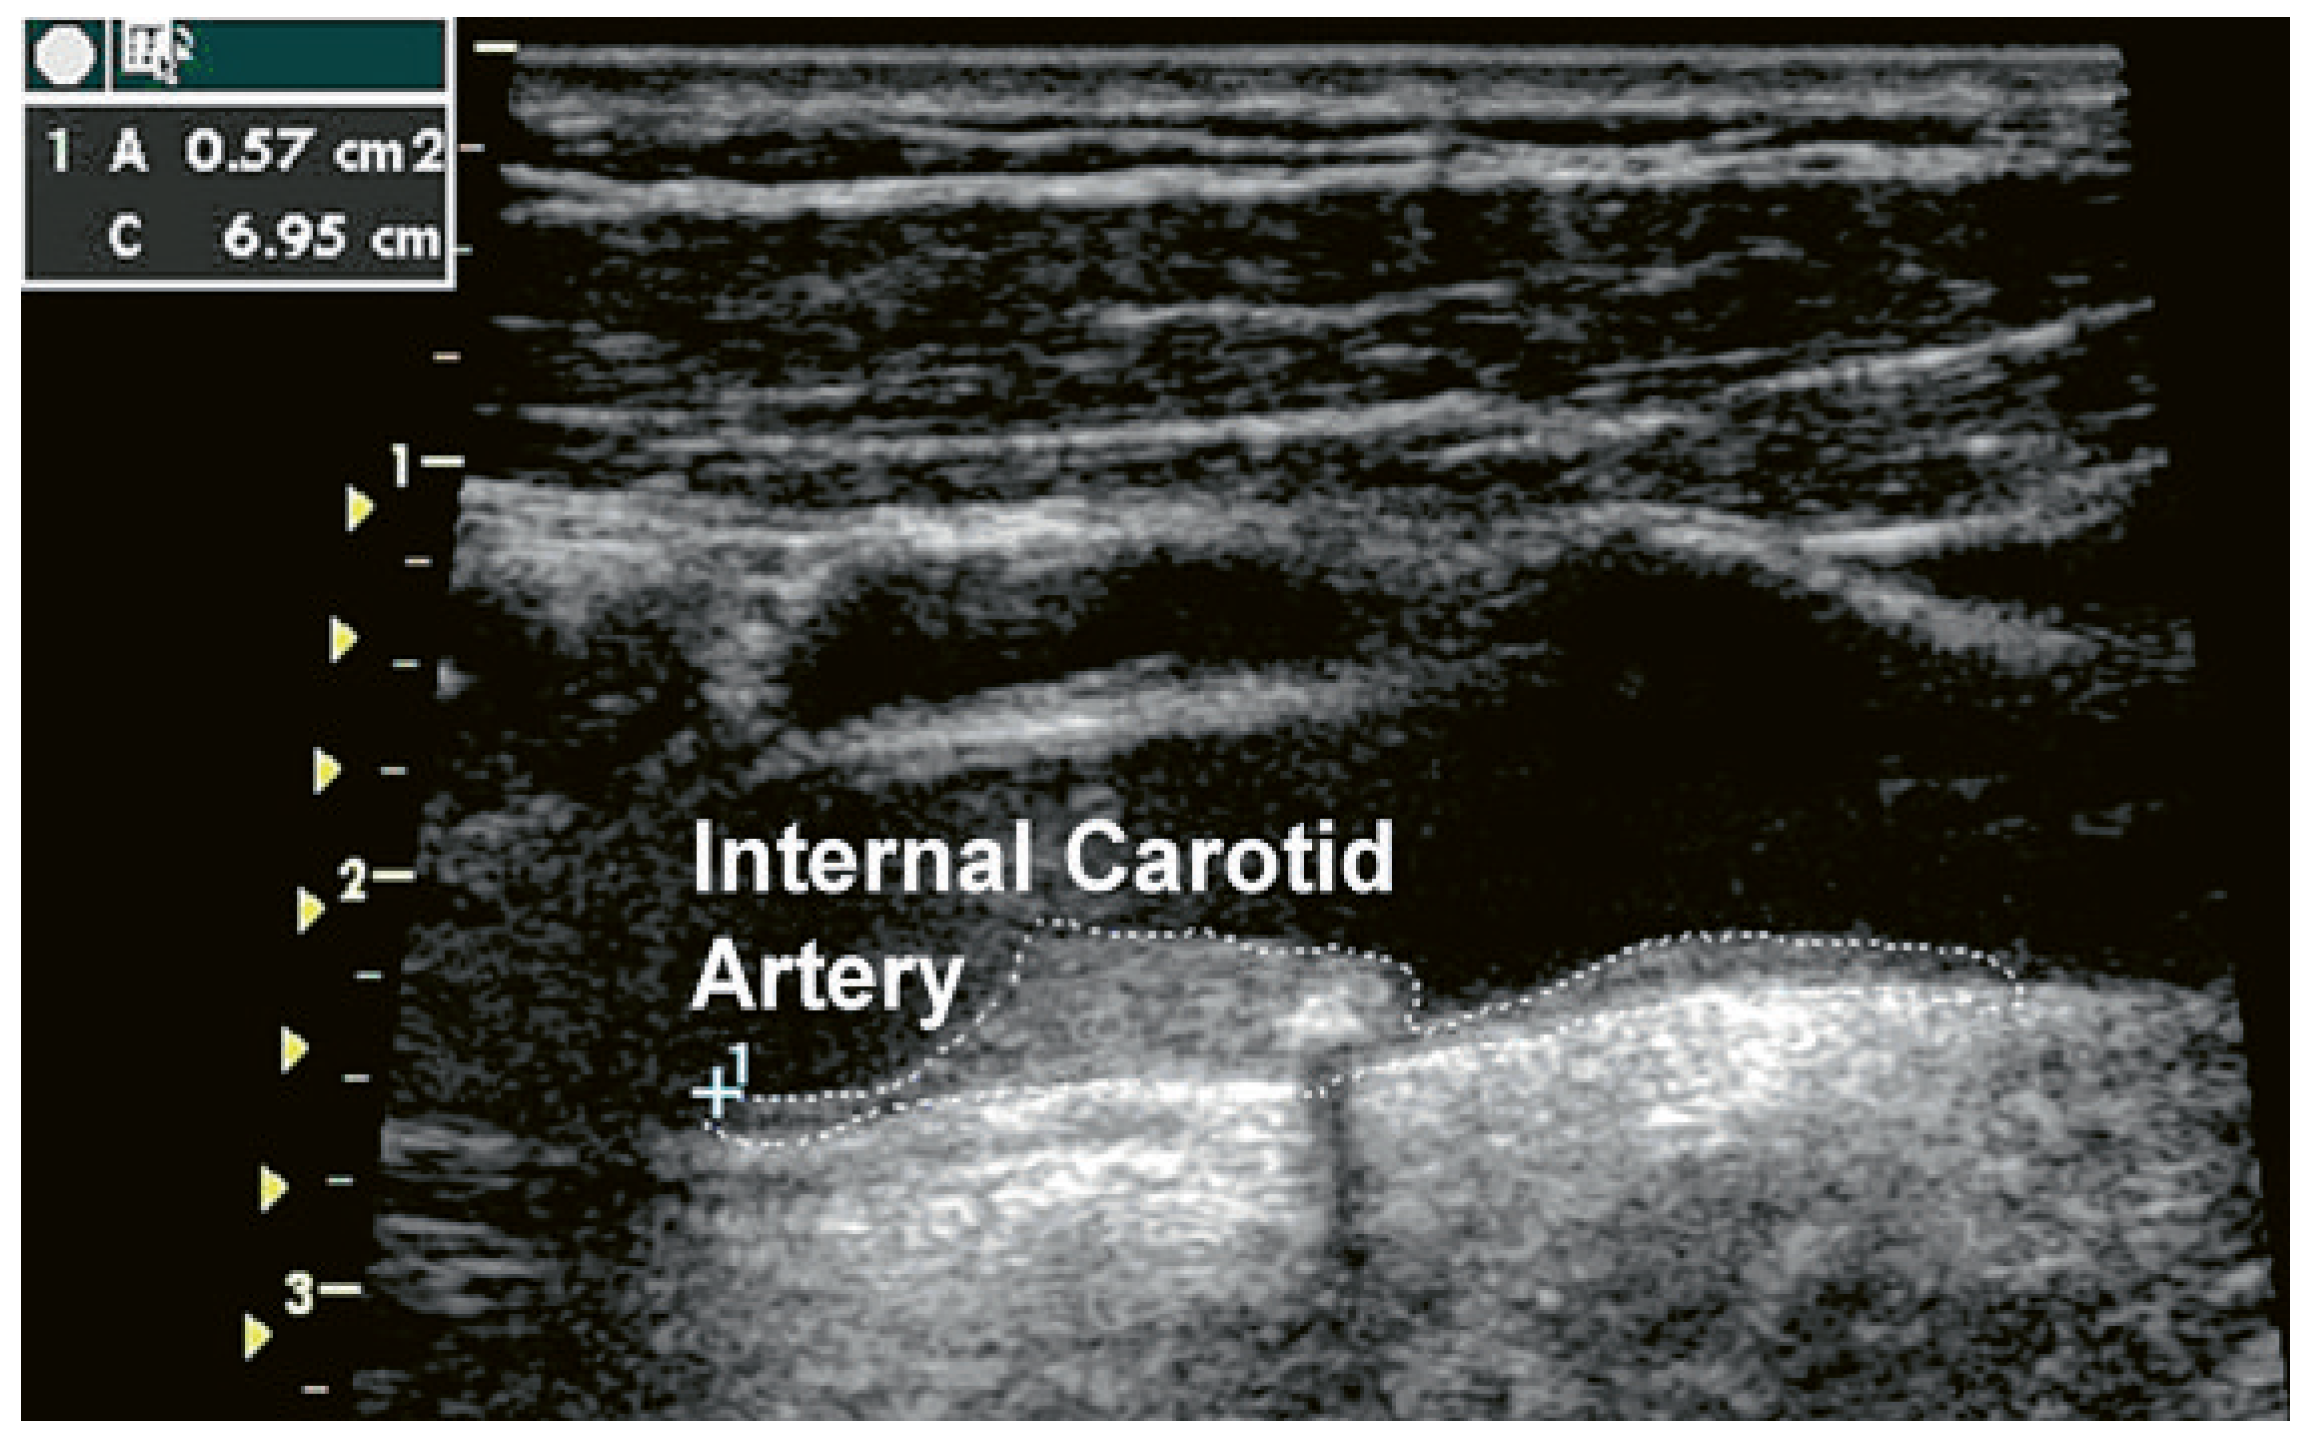

Carotid plaques may also be measured as a surface area longitudinally (Figure 2). This technique was used in the original London cohort with a large number of subjects to predict cardiovascular risk [20]. Images are acquired in the supine position. During the carotid artery examination, the patient is made comfortable in a position that allows head rotation to either side. The sonographer stands to the right of the patient’s chest. The head is rotated 35–45° away from the side examined and retroflexed by about 10–20°. Imaging is started with a transverse (short axis) sweep including the total length of the common carotid artery, the bulb, and all visible parts of the internal and external carotid arteries to check for the presence of plaque defined by a thickening >1 mm. Plaque quantification is made from a longitudinal image. Online tracing of the plaque surface is performed using calipers. The plane in which the measurement of each plaque was made is chosen by panning around the artery until the view showing the largest extent of that plaque was obtained. The sum of all plaque surface areas is defined as the total plaque area (TPA). Intraobserver reliability (intraclass correlation) was 0.94 for repeated measurements [21].

Figure 2. The figure shows an example of how plaque area can be measured in practice. In the image a single large plaque measured 0.57 cm2. The sum of all plaques within both carotid arteries is the total plaque area (TPA).